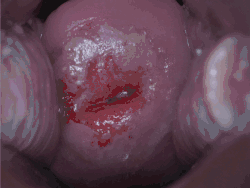

Confirmation of the diagnosis of cervical cancer or precancer requires a biopsy of the cervix. This is often done through colposcopy, a magnified visual inspection of the cervix aided by using a dilute acetic acid (e.g. vinegar) solution to highlight abnormal cells on the surface of the cervix,[5] with visual contrast provided by staining the normal tissues a mahogany brown with Lugol's iodine.[61] Medical devices used for biopsy of the cervix include punch forceps. Colposcopic impression, the estimate of disease severity based on the visual inspection, forms part of the diagnosis. Further diagnostic and treatment procedures are loop electrical excision procedure and cervical conization, in which the inner lining of the cervix is removed to be examined pathologically. These are carried out if the biopsy confirms severe cervical intraepithelial neoplasia.[62][63]